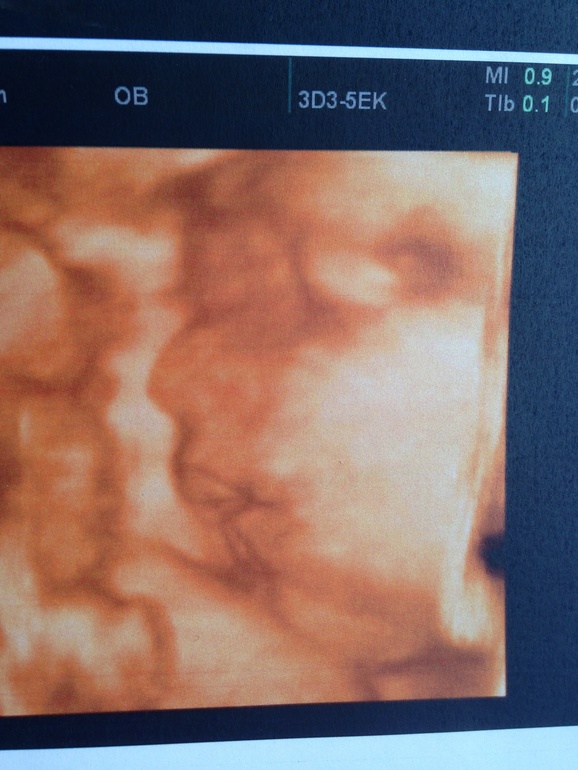

Ходили сегодня на 3d узи в ЦИР. Малыш наш в порядке!))

Срок 30-31 неделя, рост 40 см, вес 1кг400гр)